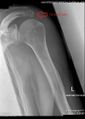

Acromion of left scapula01.png

عظم الكتف الأيسر. صورة أمامية. يظهر الأخرم باللون الأحمر.